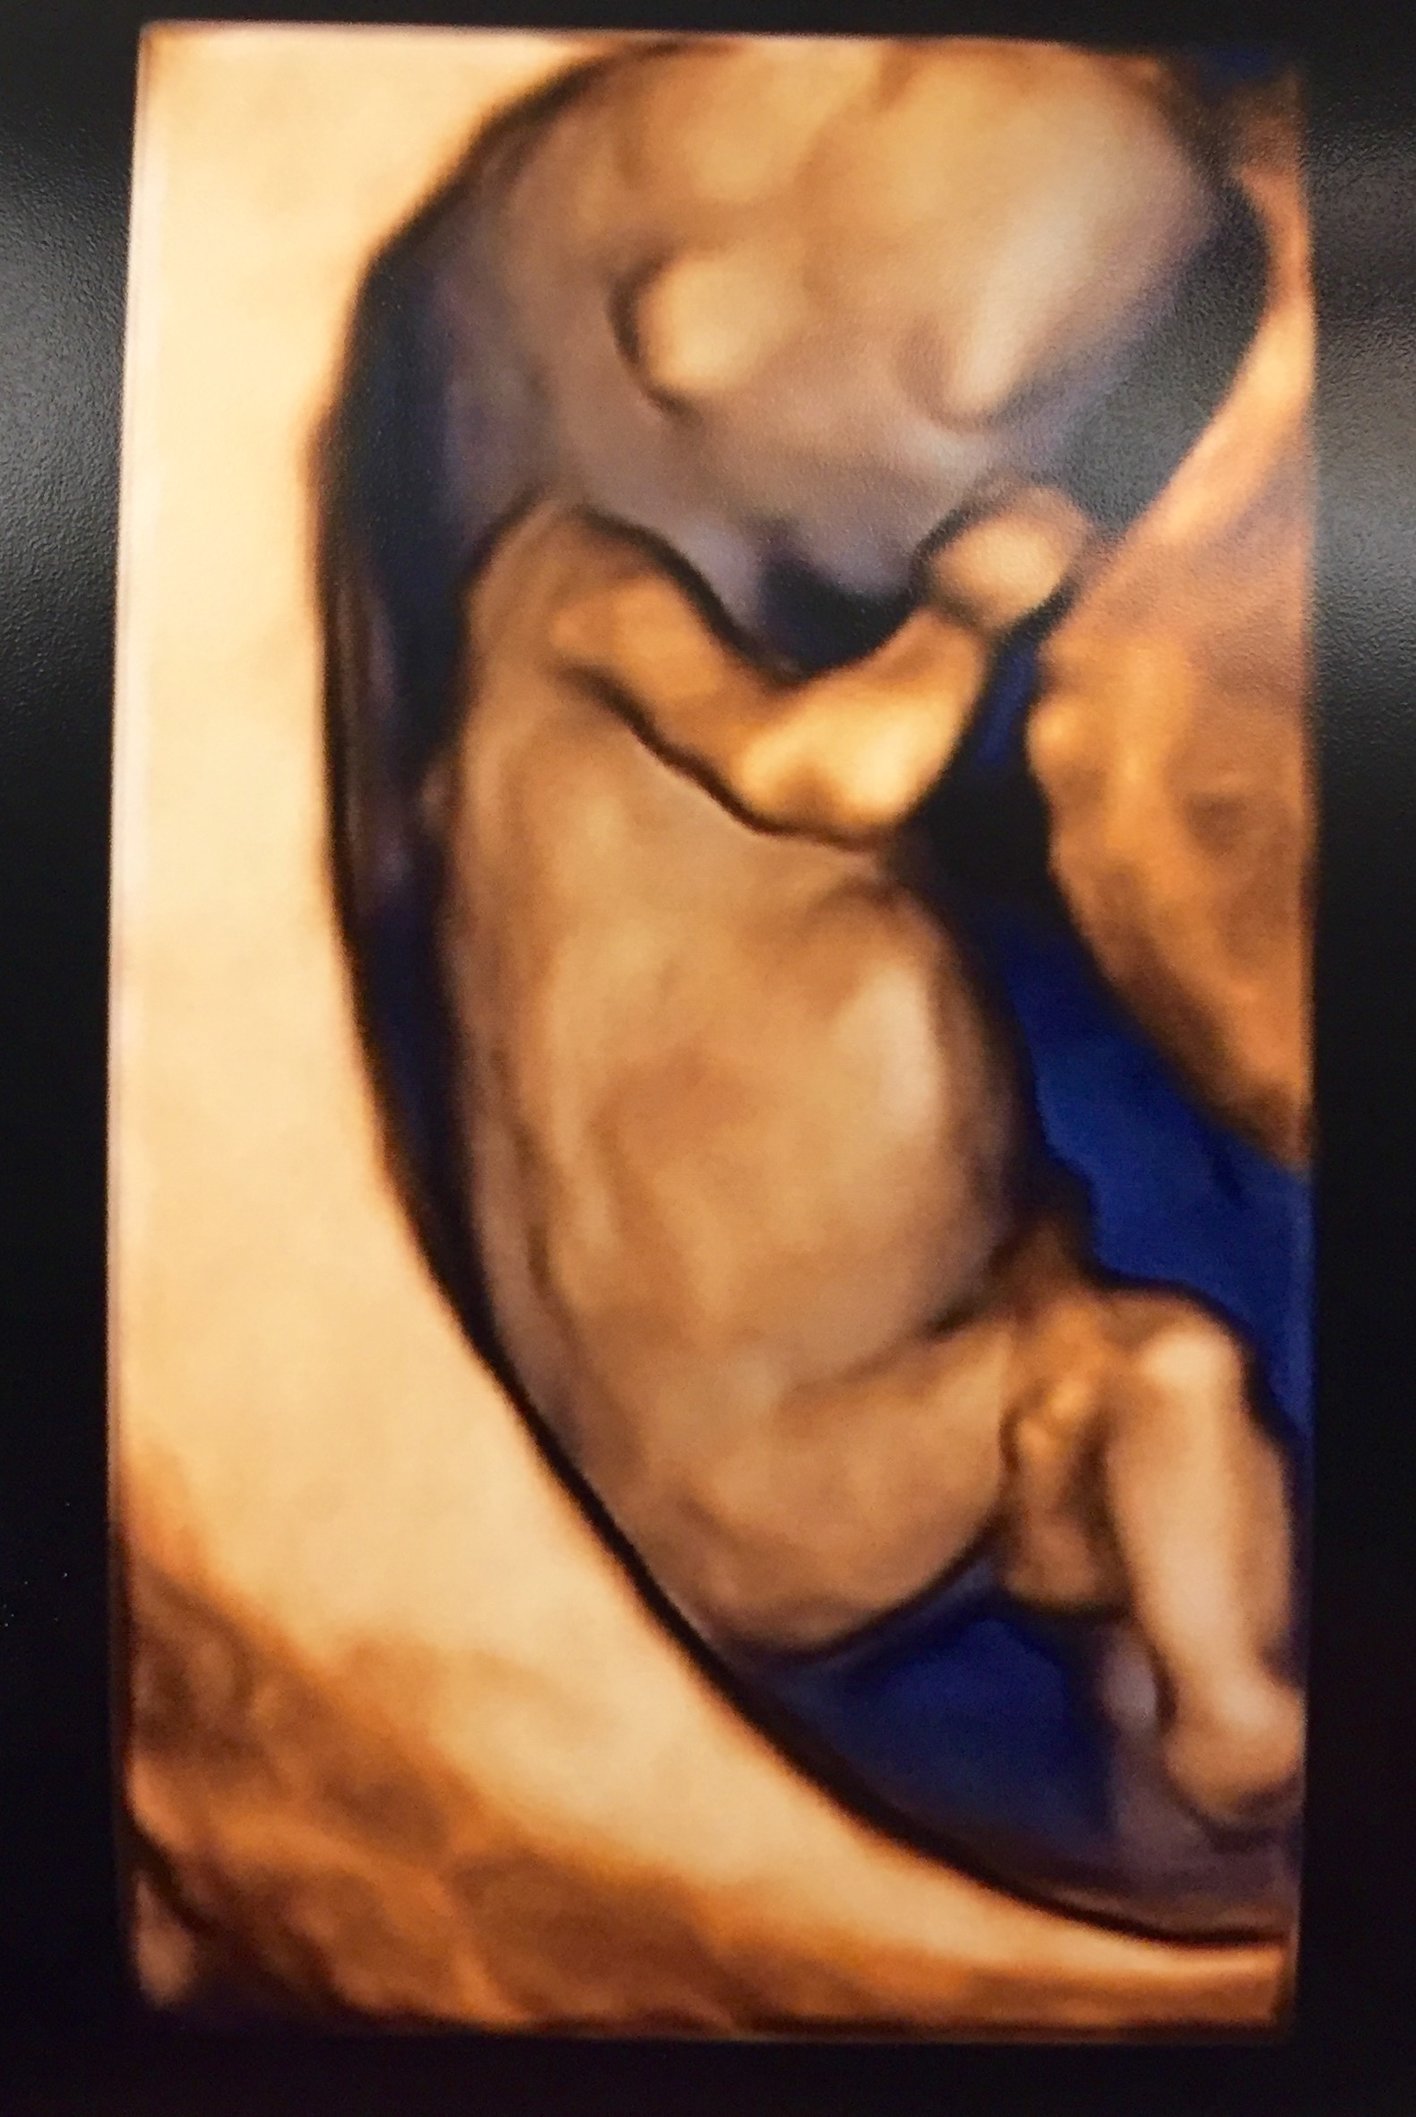

This is our little one looking more and more like a baby every day. Baby was facing the transducer and covering her face so we got some pics of her little hands and saw her cute face on the US! ETA: This was at 11w6d, baby measuring 12w3d.